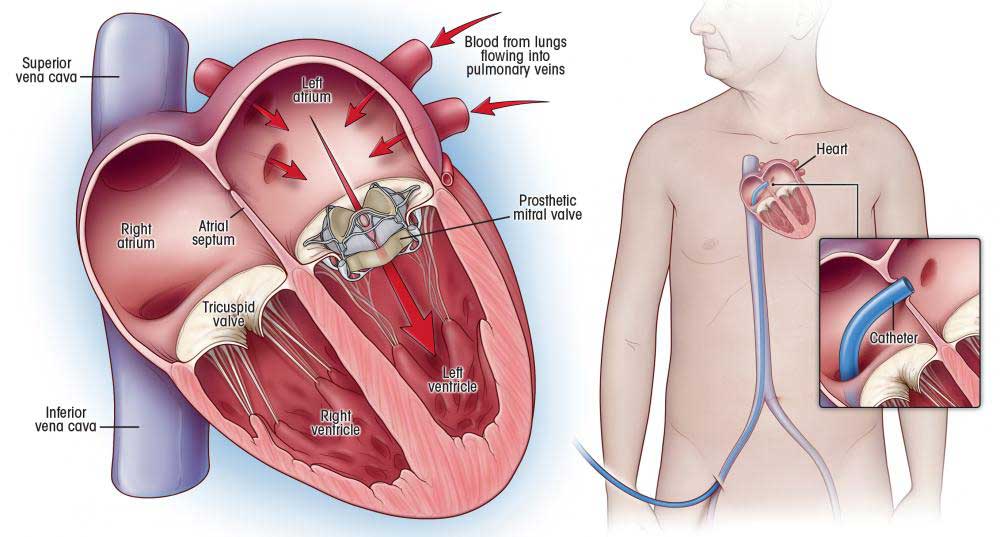

Value added benefits of the Balloon Mitral Valvuloplasty:

Ø Doctor consultation charges

Ø Lab tests and diagnostic charges

Ø Room charges inside hospital during the procedure

Ø Surgeon Fee

Ø Nursing charges

Ø Hospital surgery suite charges

Ø Anesthesia charges

Ø Routine medicines and routine consumables (bandages, dressings etc.)

Ø Food and Beverages inside hospital stay for patient and one attendant.

Extra benefits:

ü Interpreter

ü Visa assistance

Ø Site tourism of the city

Ø Follow up with the doctor

Ø Airport pick up and drop

Ø Free online consultation with the doctor

Ø Priority appointments with the doctor

Ø Room upgrade from sharing to private